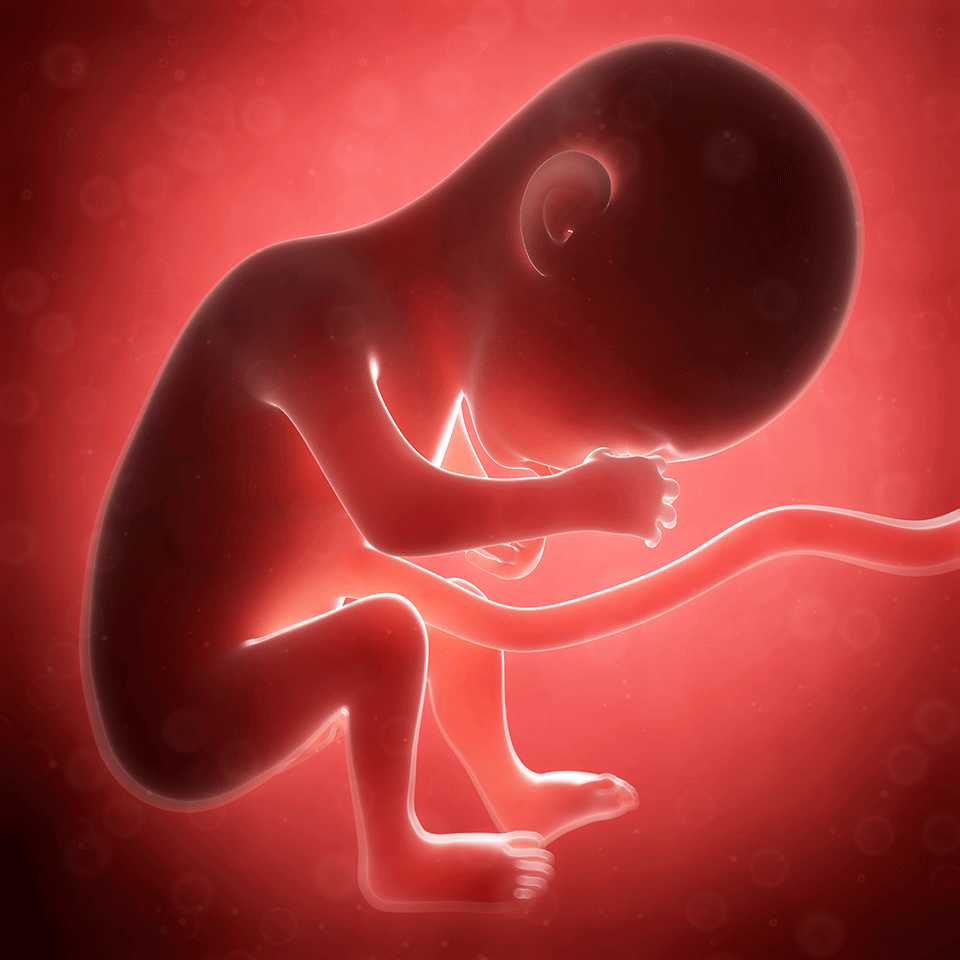

Embryo & Fetal Development – Fetus Illustration Size Comparisons

Prenatal Development | Introduction to Psychology

Fetal Development Week By Week: Stages Of Pregnancy